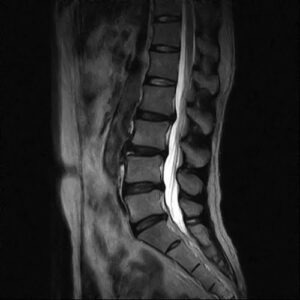

MRIなどの画像検査後にヘルニアと診断された場合は消炎鎮痛剤やブロック注射・温熱療法などをしたり痛み止めとコルセットを併用したりして自然治癒するのを待ちます。

原因不明で治療方法が見つからない方。筋肉の硬直が原因の場合、MRIやレントゲンには筋肉の硬直は写りませんので原因不明となる場合が多々あります。

MRIなどの画像診断をした結果ドクターから『それほどでも無いけどあえて言うならヘルニア』とか『ほんの少しヘルニアになっている』などと言われた方も痛みの原因はヘルニアには無い場合が殆です。

単に検査した画像で骨格標本との違いを探してもヘルニアの痛みの本当の原因は見つかりません。